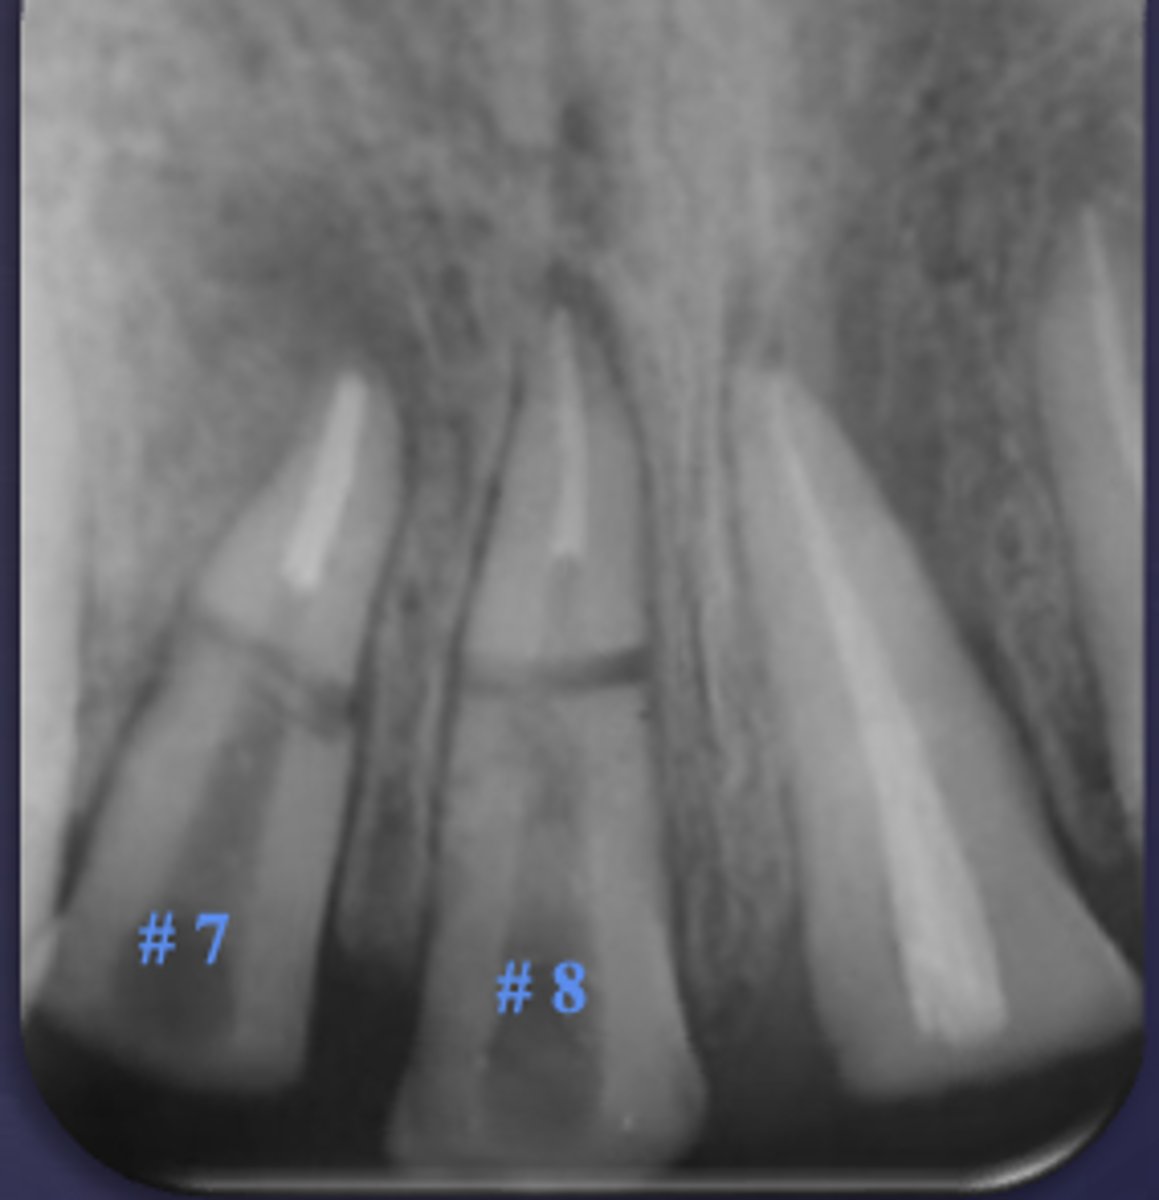

ID the condition:

Carious exposure of pulp

Root fracture